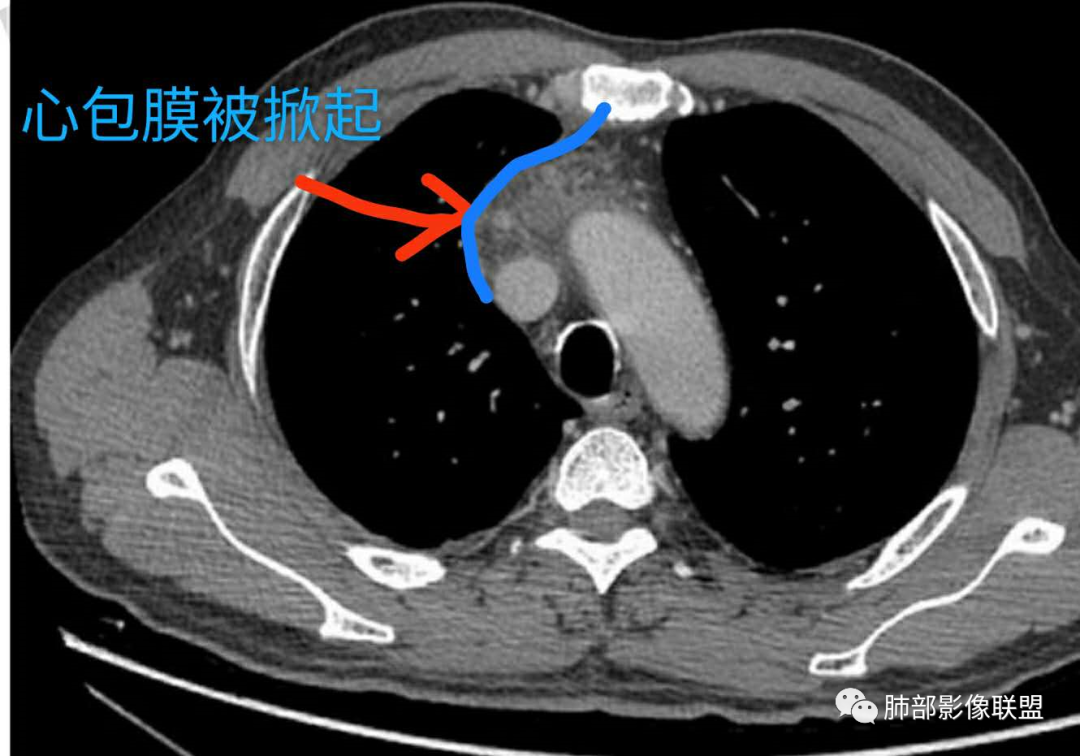

2.胸膜掀起,右侧内乳动脉略增粗,定位右前上纵隔内占位。

4.四天内病灶变化快,块影增大且不规则,包膜似不完整,边界不清,上份可见浸润或渗出,与周围心脏大血管及心包等间隙不清。胸水增多。

第一次的检查符合胸腺瘤影像学改变,短期内的形态学改变及突然出现的边界模糊或浸润等,符合出血或炎症。